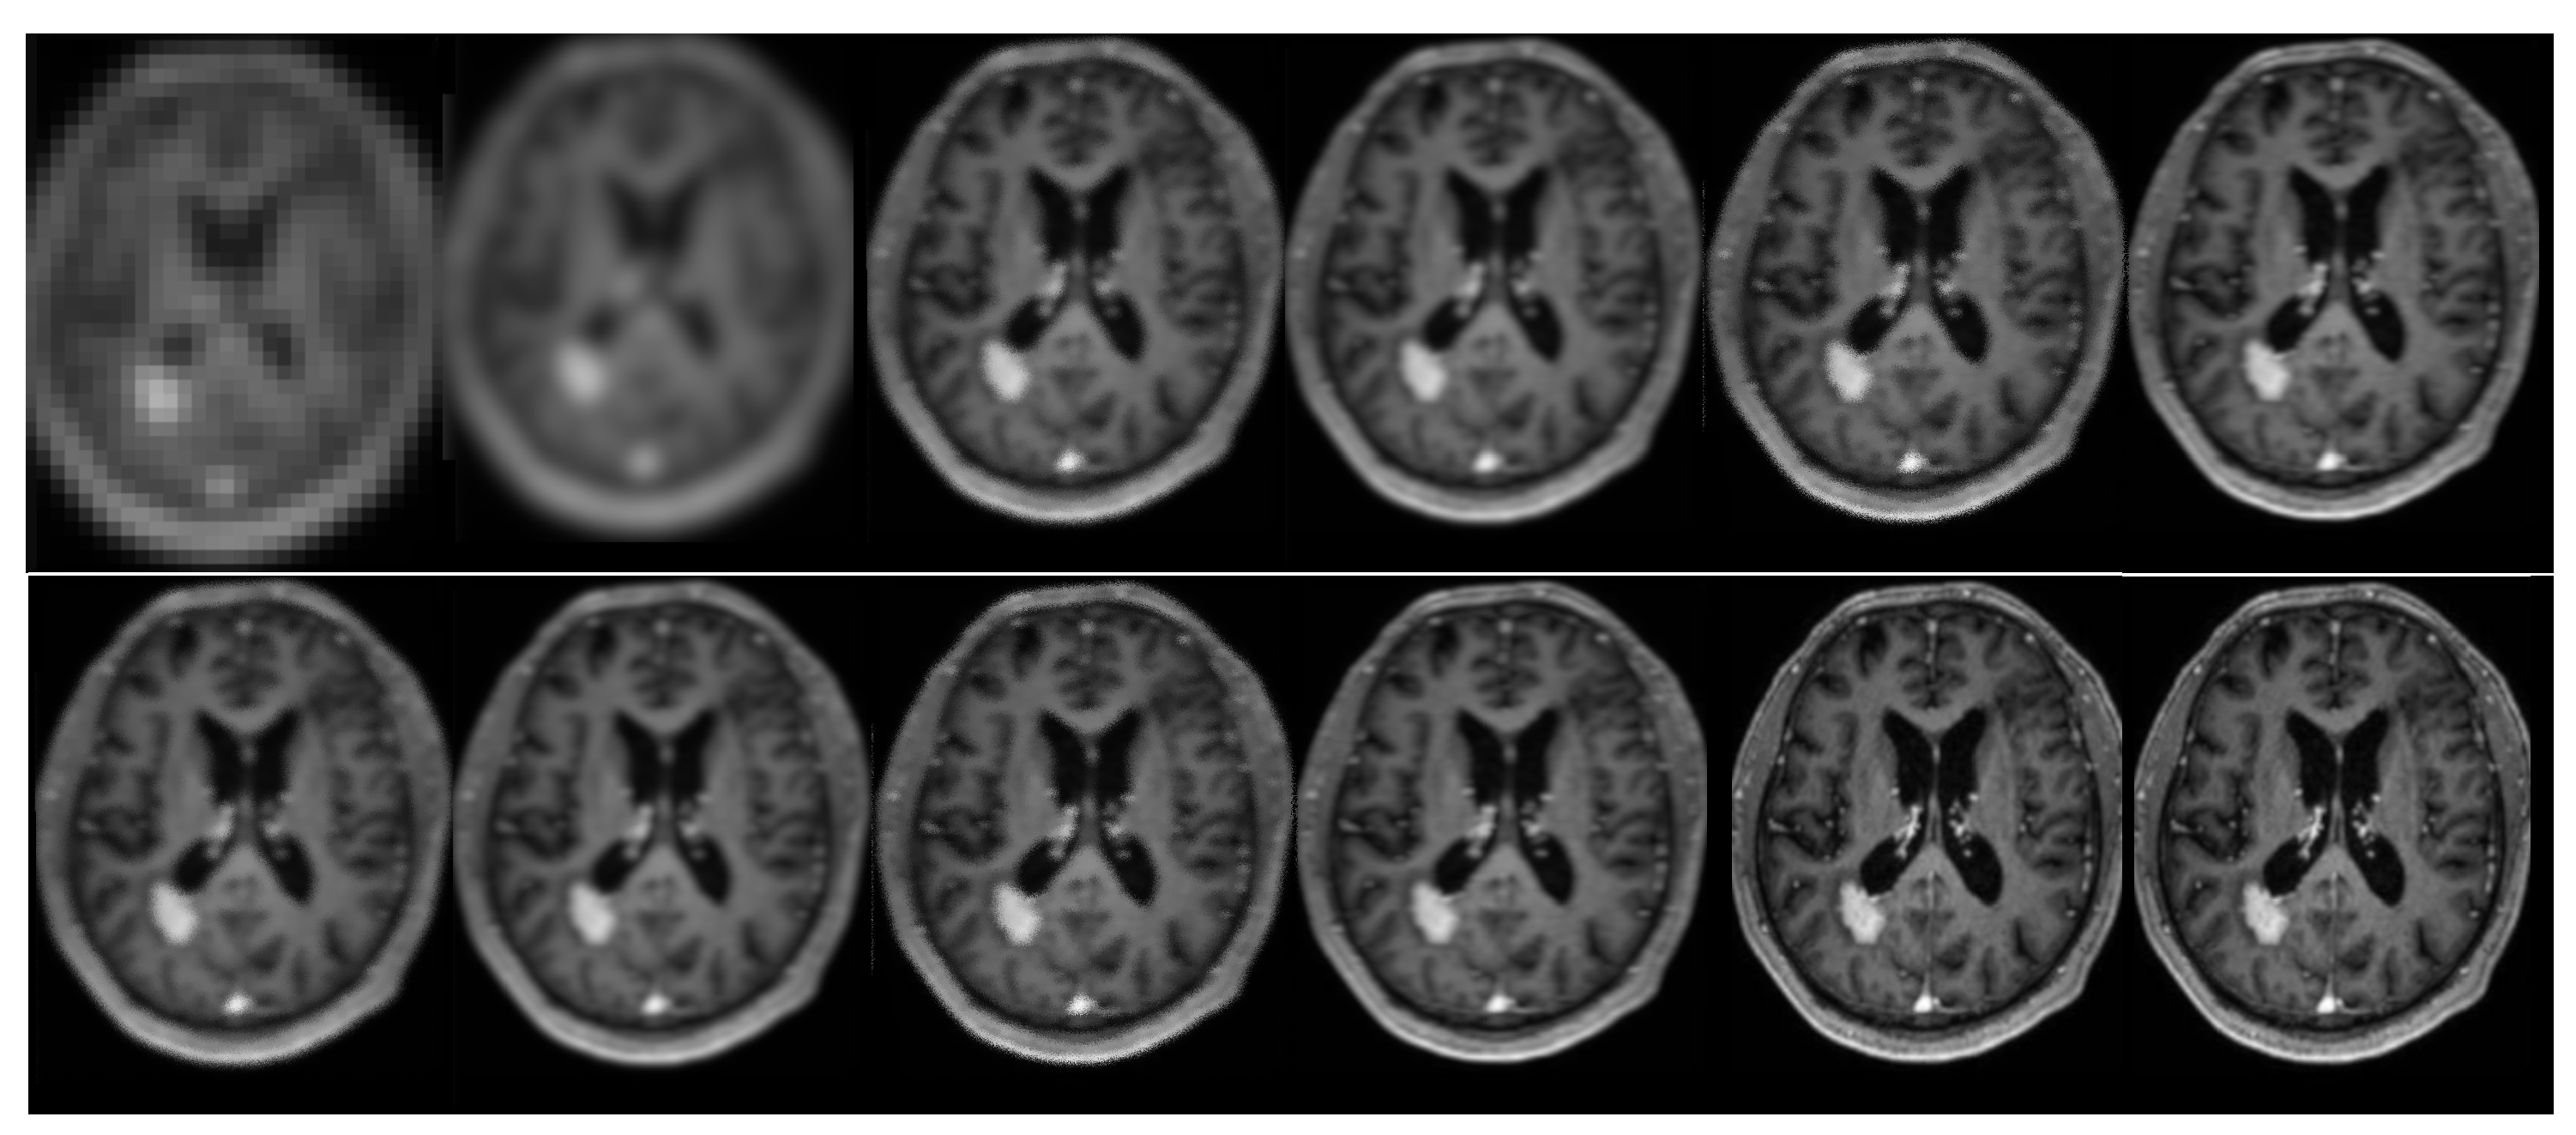

Figure 10. The results of the second phase of the clinical brain imaging trial. The current study focuses on the reconstruction of an image using various techniques. In the first row, the regular sampling scheme is utilized without motion correction and SRR applied (1) (PSNR = 21.26 dB). The reconstruction process involves the use of the B-spline curve (2) (PSNR = 23.29 dB), Yang’s method [50] (3) (PSNR = 26.41 dB), Lim’s method (4) (PSNR = 29.22 dB) as referenced in [20], Zhang’s procedure (5) (PSNR = 28.71 dB) as referenced in [51], and Zhang’s second algorithm (6) as referenced in [43] (PSNR = 29.89 dB). In the second row, Mahapatra’s method [52] (7) (PSNR = 29.14 dB) and Wang et al.’s [53] procedure (8) (PSNR = 30.11 dB) are employed. Furthermore, the reconstruction procedure utilized Guerreiro’s approach [54] (9) (PSNR = 29.77 dB), Pham et al.’s method [55] (10) (PSNR = 23.48 dB), Shi’s method [17] (11) (12) (PSNR = 30.01 dB), as well as the author’s method (12) (PSNR = 32.61 dB). Furthermore, in order to achieve super-resolution, a suggested sampling strategy and motion correction techniques were employed. The aforementioned procedures were implemented without the inclusion of supplementary data. The compression ratio is 50%.